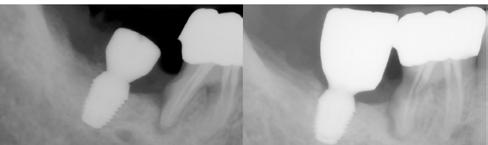

A CT metszetekben a 48-as gyökerei körbeölelik a canalis mandibularist, amelyet piros nyíllal jelöltünk a fotókon.

Szeretnék mutatni néhány ábrát az egyik bonyolult esetről, a közelmúltból. A CT-n látszik, hogy a három gyökér teljesen „körbenőtte” az ideget. Van olyan frontális metszeti kép, ahol csak a gyökerek vannak a nervus körül, ezen a szakaszon egyáltalán nincs meg a csontos fala a canalisnak. Szeparációs technikával, viszonylag könnyen, minimális traumával, szövődménymentesen sikerült eltávolítani a fog minden részét. A várakozásnak megfelelően, a beteg nem számolt be paraesthesiáról.